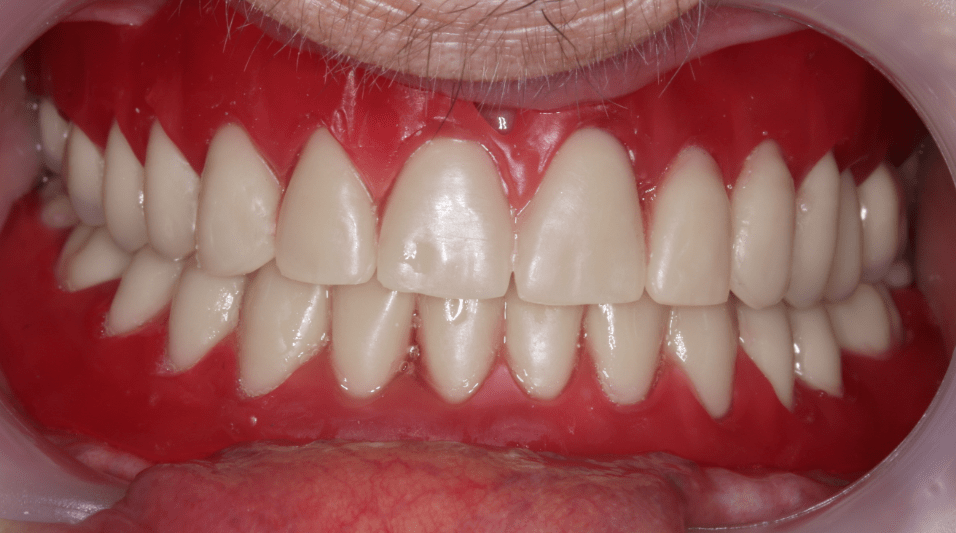

Páciensünk maradéktalanul boldog volt új fogpótlásaival - és ezt egy kedves mosollyal ki is mutatta!

Fogpótlás teljes lemezes átadás után szájban